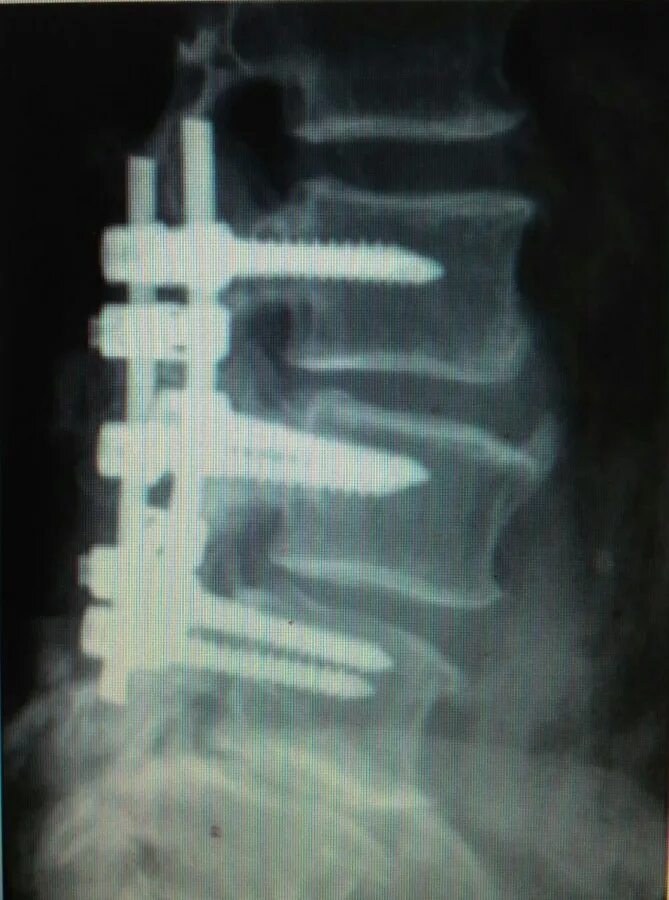

Смещение позвонков поясничного операция